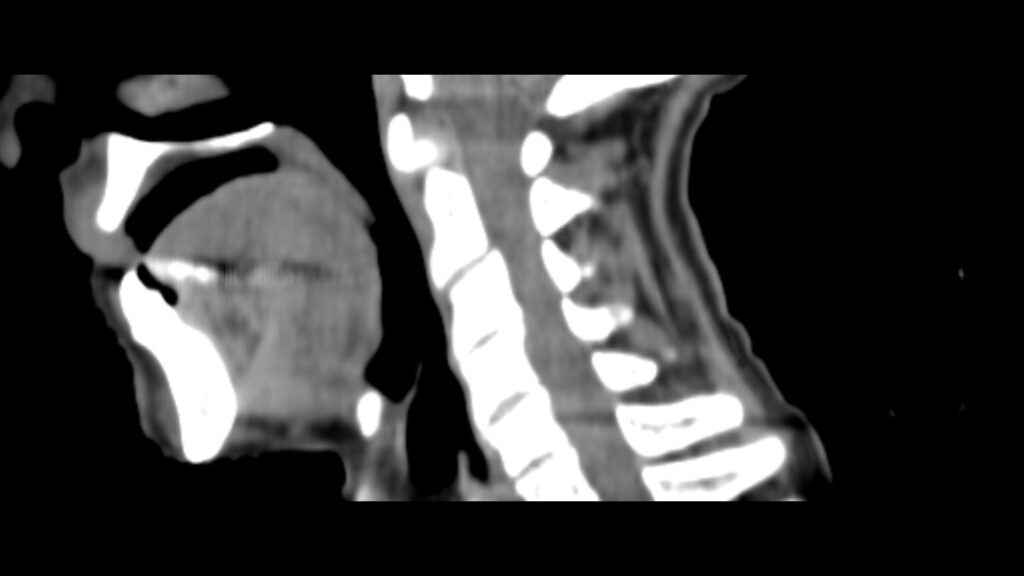

Planning CT Images